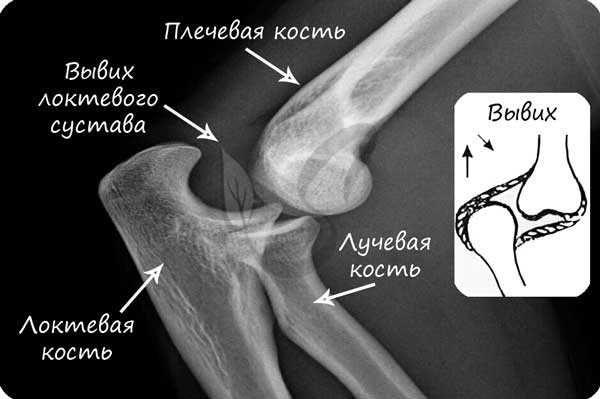

В норме кости могут смещаться относительно друг друга в суставе, однако при травме, слишком резком и сильном движении это смещение может быть слишком сильным: в результате нарушается соприкосновение суставных поверхностей. В таком случае говорят о возникновении вывиха.

Вывих - смещение суставных концов костей, как с нарушением целостности суставной капсулы, так и без нарушения.

Перед вправлением вывиха следует делать рентгенологическое исследование, чтобы убедиться в отсутствии переломов костей, которые иногда сопутствуют вывиху.